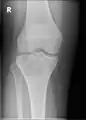

A variety of imaging studies can be used to diagnose chondroblastoma, with radiographs being the most common.[10][8] Laboratory studies are not considered useful.[14] Classical chondroblastoma (appearing on long bones) appears as a well-defined eccentric oval or round lytic lesion that usually involves the adjacent bone cortex without periosteal reaction.[10][13] A sclerotic margin can be seen in some cases.[10][13] For long bone chondroblastomas the tumor is typically contained to the epiphysis or apophysis but may extend through the epiphyseal plate.[10][13] Chondroblastomas are usually located in the medullary portion of bones and can, in some cases, include the metaphysis.[10][13] However, true metaphyseal chondroblastomas are rare and are typically the result of an extension from a neighboring epiphyseal legion.[10][13] Most lesions are less than 4 cm.[10] A mottled appearance on the radiograph is not atypical and indicates areas of calcification which is commonly associated with skeletally immature patients.[10] Additionally, one-third of all cases involve aneurysmal bone cysts which are thought to be the result of stress, trauma or hemorrhage.[10] In cases involving older patients or flat bones, typical radiographic presentation is not as common and may mimic aggressive processes.[10][13]

1. a. X-ray of chondroblastoma of thigh bone near knee

2. X-ray of chondroblastoma of shoulder blade